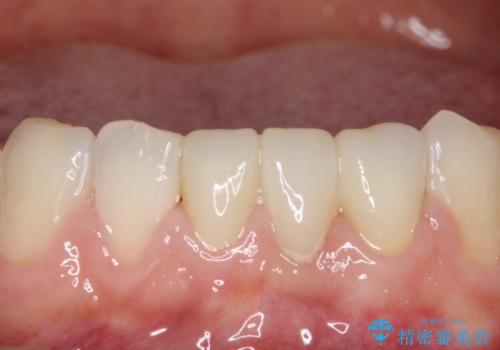

発見の難しい虫歯。根管治療から被せもの治療

根管治療から被せもの治療(ベレッツァ)まで行いました。(根管治療は林院長に依頼)

妥協せずにすべての治療を行うことで最終的な被せものの適合を高める事ができます。